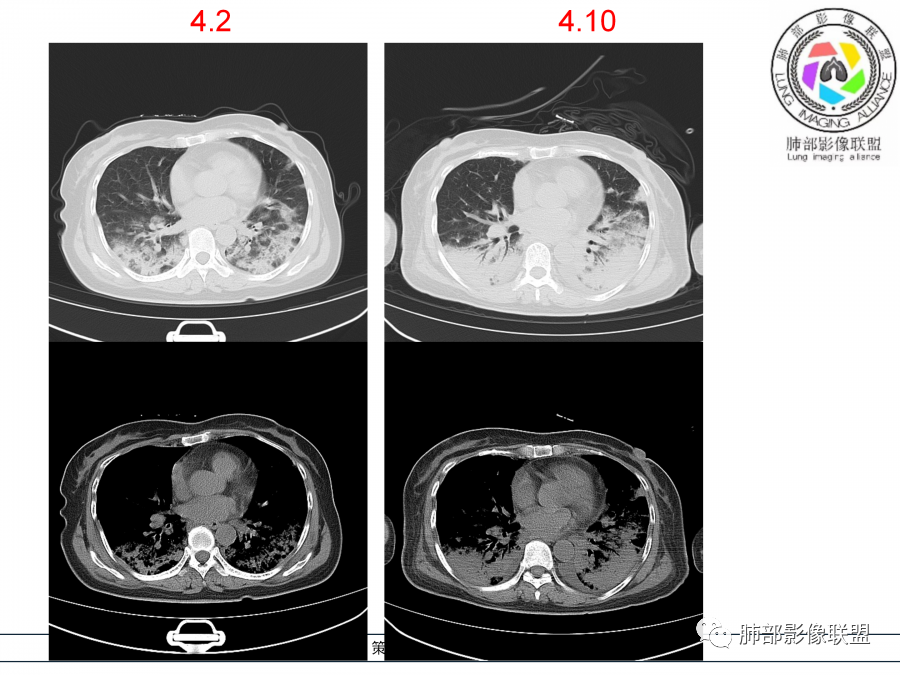

影像,第一次双肺中下叶胸膜下多发斑片状实变影,部分融合成,周围散发磨玻璃影,磨玻璃影内可见小叶间隔及小叶内间隔增厚,病变平行于胸膜,第二次间隔8天,双肺实变影明显进展,有重力作用,支气管近端堵塞,进展较快,临床有发热,血沉高,狼疮SLE阳性,考虑1:OP(机化性肺炎)2:SLE相关肺炎,建议支气管镜灌洗液病原学检测。

➢患者7天前起因受凉后出现阵发性咳嗽,无明显时间规律性,咳黄白粘痰,发热,体温最高达39.5℃,伴鼻塞、流清涕,。两肺下叶背段,后基底段为主的渗出性的病变,短时间内病变明显的增多,双侧胸腔积液,狼疮全套抗R0/SS检测阳性,考虑狼疮性肺损,机化性肺炎?鉴别结核

老年女性,咳嗽咳痰伴发热7天,白细胞不高,血沉快,降钙素原不高。其他化验未见明显异常,狼疮全套抗Ro/SSA阳性,双肺野靠近胸膜下磨玻璃实变影,支气管通畅,有充气征,沿胸膜下分布,有细网格征,7天后进展明显,实变影加重,胸膜肥厚,胸水不明显,心包少量积液?抗感染治疗无效,考虑非感染性疾病可能性大,结缔组织相关性肺病?狼疮性肺炎?机化性肺炎?鉴别病毒性肺炎。

老年女性,咳嗽咳痰发热7天。无气促。白细胞计数不高,PCT稍高,PPD(+),抗Ro/SSA阳性。CT:双肺野靠近胸膜下磨玻璃实变影,支气管通畅,有充气征,沿胸膜下分布,有细网格征。予抗生素治疗,8天后复查胸部CT见病灶范围扩大,实变影加重,胸膜肥厚,胸水不明显。抗感染治疗无效,考虑有:1.非感染性疾病:结缔组织相关性肺病,支持点:肺部CT表现为间质性炎症病变,抗RO/SSA(52)阳性;2.病毒性肺炎:患者无气促症状,可能性小;3.肺结核。

第一次双肺中下叶胸膜下多发斑片状磨玻璃及实变影,病变平行于胸膜,支气管通畅,8天后,双肺实变影明显进展范围扩大,部分支气管近端堵塞,进展较快,胸腔积液,抗感染治疗无效,考虑:非感染性疾病:结缔组织相关性肺病。鉴别机化性肺炎。